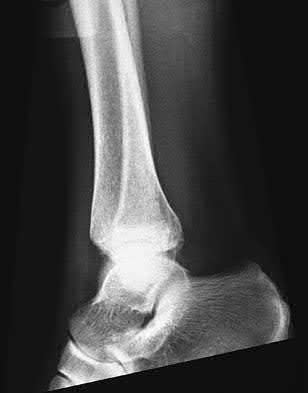

A 25-year-old female is involved in a motor vehicle collision. She presents with the isolated injury seen in Figures A through D. Her leg is swollen but her skin is intact. She has no clinical signs of compartment syndrome. Which of the following treatment options will allow for maintenance of fracture alignment and minimize the risk of soft tissue complications?

The patient presents with a closed distal third metaphyseal-diaphyseal distal tibia fracture with simple intra-articular extension. Immediate intramedullary nailing along with percutaneous fixation of the articular component provides appropriate restoration of length, rotation and alignment and minimizes the risk of wound complication.

Displaced distal third tibia fractures may be associated with simple intraarticular extension. Operative treatment of intra-articular distal tibia fractures has historically been performed with open reduction and internal fixation. Early open reduction and plate fixation of pilon fractures has been associated with high rates of infection and wound complication. In select patterns with simple articular extension, percutaneous screw fixation and medullary nailing may provide appropriate reduction with minimal soft-tissue risk.

Figures A and B demonstrate a distal third tibial shaft fracture with simple intra-articular extension. The axial and coronal CT cuts in Figures C and D further clarify the articular injury. Illustrations A and B demonstrate a comminuted distal third tibial fracture with simple intra-articular extension. Illustrations C and D are fluoroscopic images of the same injury after intramedullary nailing and percutaneous fixation of the articular component.